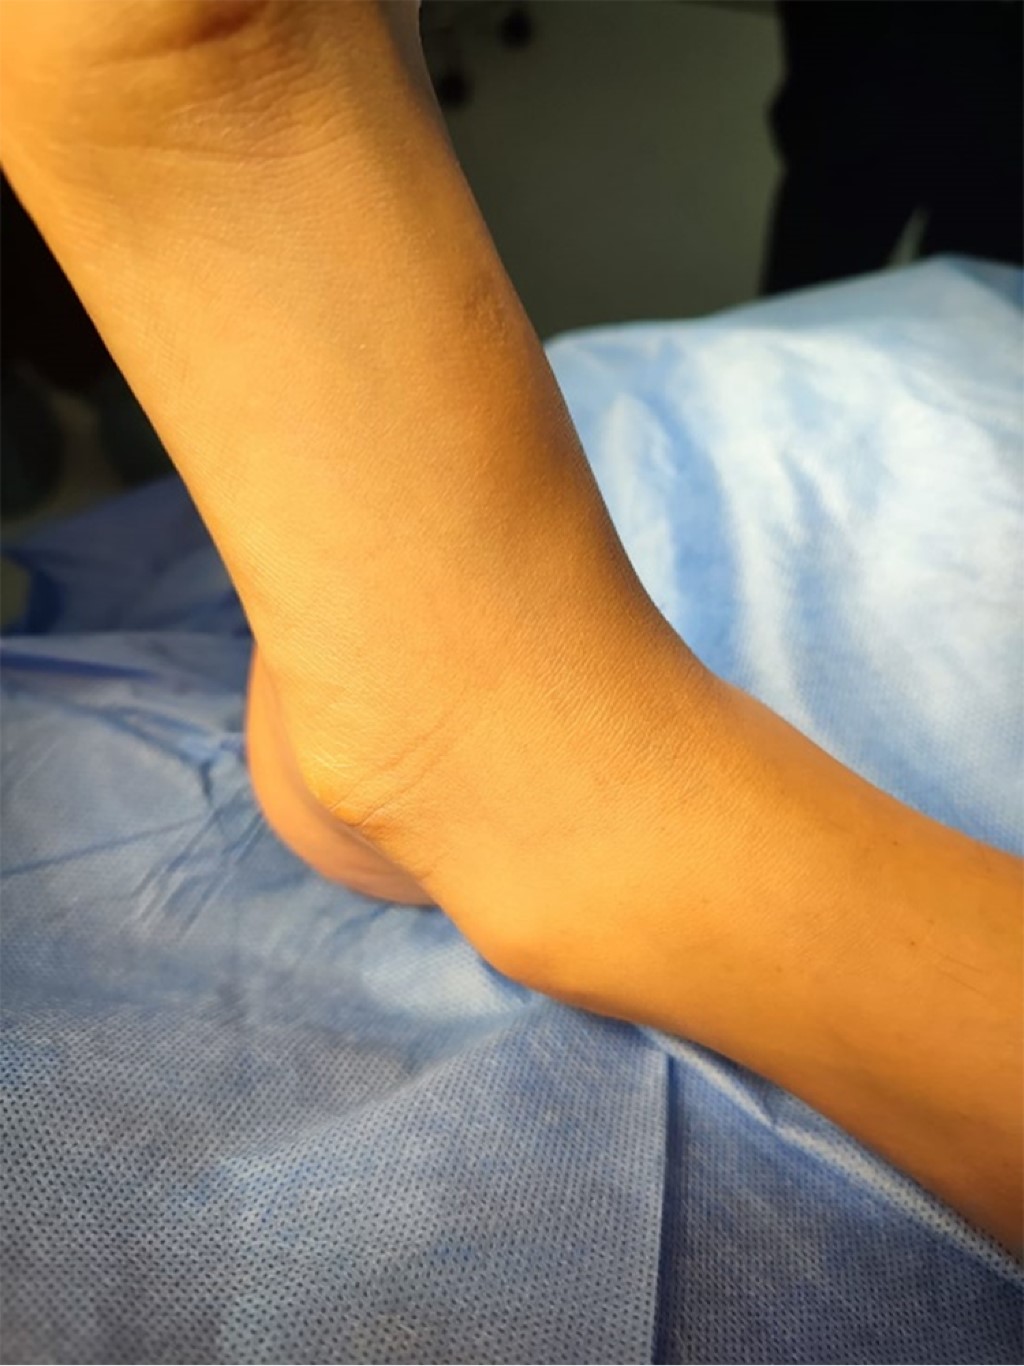

Masculino de 14 años que presentaba tres meses de dolor en cara interna de pie derecho, sin trauma (Figura 1). Al realizar la exploración se notó claudicación, talo valgo, pronación de antepié, dolor en escafoides tarsiano, sin pie plano. En la radiografía dorsoplantar y oblicua se evidenció prominencia unida al escafoides por puente óseo (tipo III) (Figura 2). Se optó por tratamiento conservador (descarga, analgésicos orales y tópicos) durante dos semanas, pero no hubo mejoría, por lo que se propuso cirugía.

Figura 1